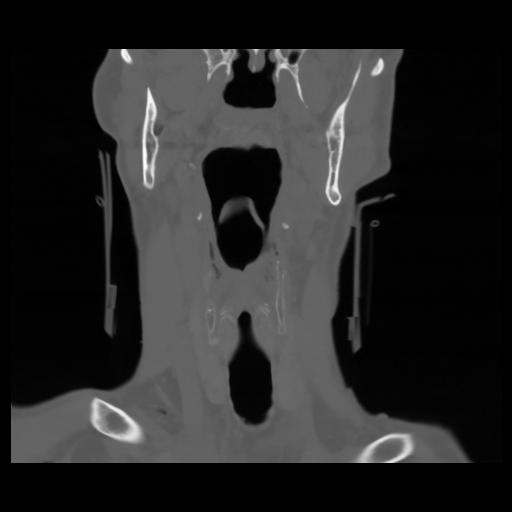

13 P.BLANDAS,,Coronal,2.000,P.BLANDAS,Coronal,